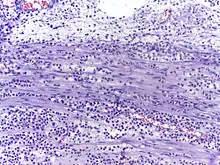

Micrograph showing several neutrophils during an acute inflammation

Low neutrophil counts are termed neutropenia. This can be congenital (developed at or before birth) or it can develop later, as in the case of aplastic anemia or some kinds of leukemia. It can also be a side-effect of medication, most prominently chemotherapy. Neutropenia makes an individual highly susceptible to infections. It can also be the result of colonization by intracellular neutrophilic parasites.